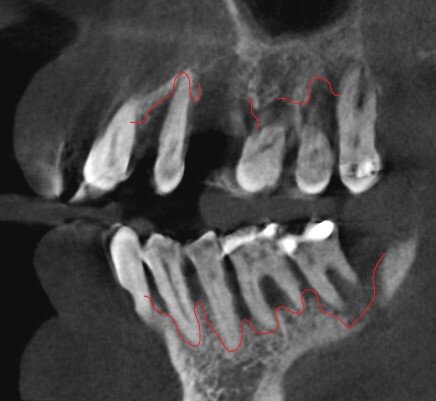

Давно разрушенные корни зубов - развился периодонтит.

Большие периапикальные очаги деструкции костной ткани.

Что делаем в случае этого пациента?

Удаляем корни зубов и ждём 4-6 месяцев, пока кость полностью восстановится. Прогноз - отличный.

Имплантацию одномоментно в таких условиях проводить не разумно.

Прикус. Мезиальный. Нижняя челюсть впереди верхней.

Мезиальный прикус.

Посмотрим снимок КТ.

Доказательство разности кости.

Но вы скажете - зона же нас другая интересует! Какие проблемы?

Проблемы глобальные.

Собственные зубы и кость пациентов с мезиальным прикусом приспособились вот к такой жизни - зоны роста как бы выдвинуты. Ох, ну и оборот, но как ещё объяснить? Наклон имеют зубы, наклон имеет кость, в которой эти зубы находятся.